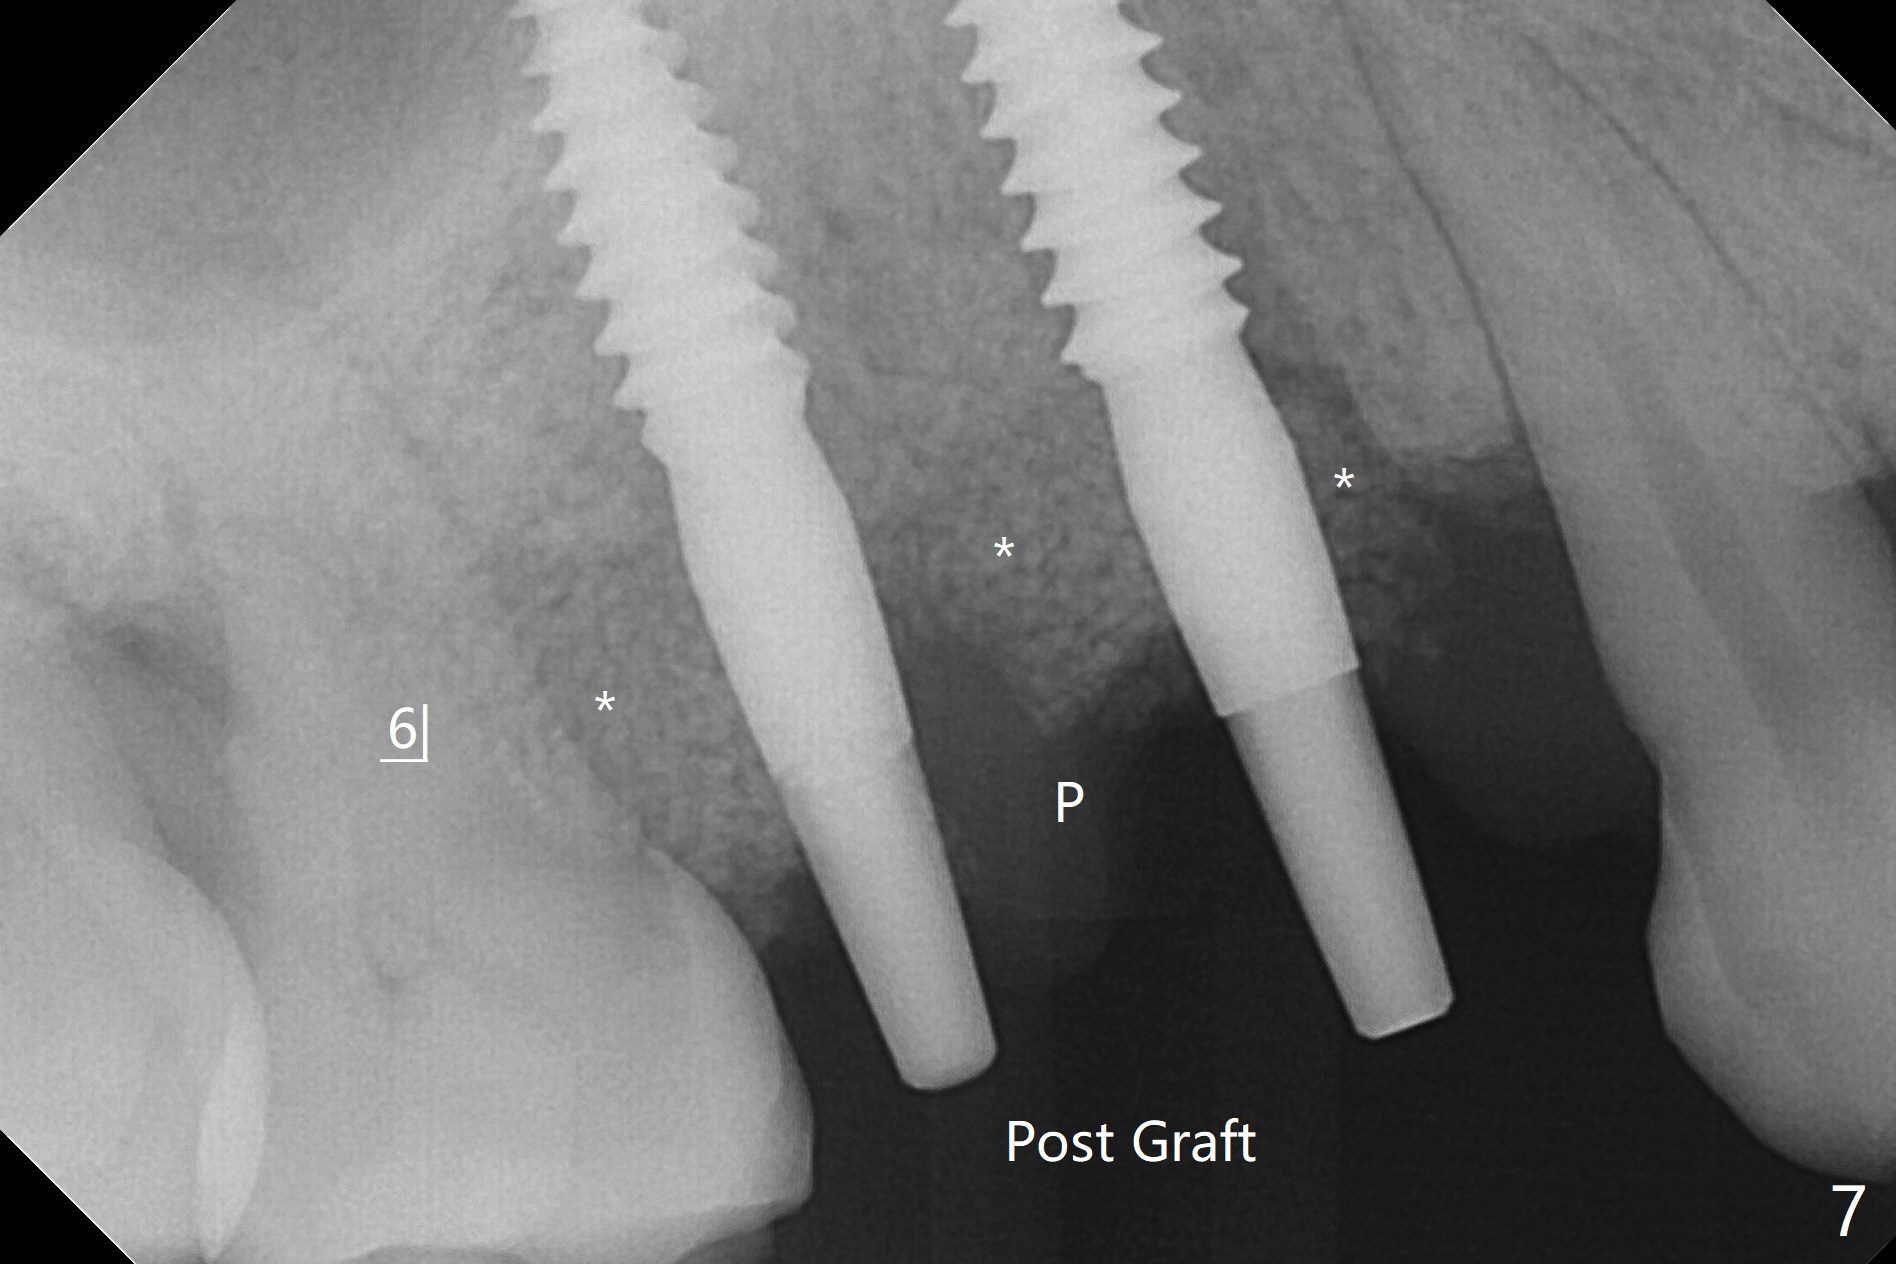

术前CT显示右上4牙槽骨比5窄(图一,二),3.5毫米植体比较合适,况且牙龈厚,基台长的一段式植体显得得当。为了取得最好的植体方位,4先拔除(图三),种植(图四),调整后者深度后,拔除5(术前征求病人同意),开始钻洞(图五),完成种植(图六)。粘性骨粉不仅放置于植体周围,而且6牙根近中(图七),4/5牙槽嵴和龈乳头(P)之间,减少术后龈乳头萎缩(图八:*)。制作两个分开临时牙冠,有利于维持龈乳头。对于病人来说,临时牙冠帮助咀嚼,而对侧拔牙创无法吃饭。术后3个月两个分开临时牙冠(其中一个龈方移位(图九:箭头)保持龈乳头(*)和牙龈外形(图十:*)。临时牙冠取出后,调整基台高度,少量钛屑(不妨大局)附着在健康的牙龈沟(图十一),再次显示两个基台之间龈乳头(图十二:*),衬里,修整的临时牙冠又插回牙龈沟(图十三:箭头),继续维持软组织形态,准备一个月后,调整基台边缘(图十二:箭头),取模。术后五个月大部分骨粉依然保留在植体和邻牙周围,龈乳头退缩不多(图十四: P)。三个月后(术后六个月)钛削无影无踪(图十五,与图十一对比))。永久性牙冠周围空间慢慢会消失(图十六,使用临时性胶水)。